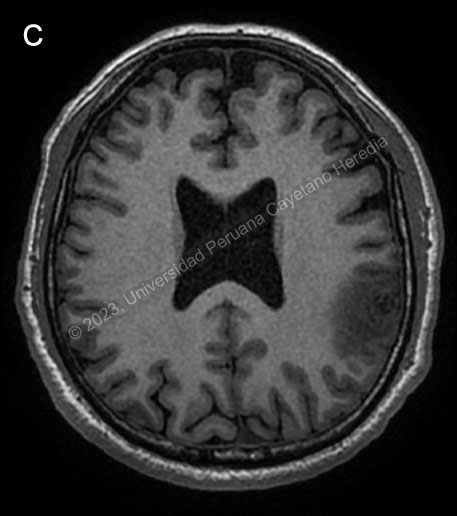

Diagnosis: Parenchymal neurocysticercosis

![]() Discussion: Brain CT showed a calcified lesion with surrounding edema in the left parietal lobe and additional calcified nodular lesions with no edema in the left occipital lobe. The lower limb x-ray showed a cigar-shaped calcification compatible with a calcified cysticercus. Brain MRI (Image C) confirmed these findings, showing an irregular nodular cortico-subcortical lesion of heterogenous aspect with peripheral vasogenic edema in the left parietal lobe, and the previously described left occipital lesions. A diagnosis of neurocysticercosis was made with these images. |